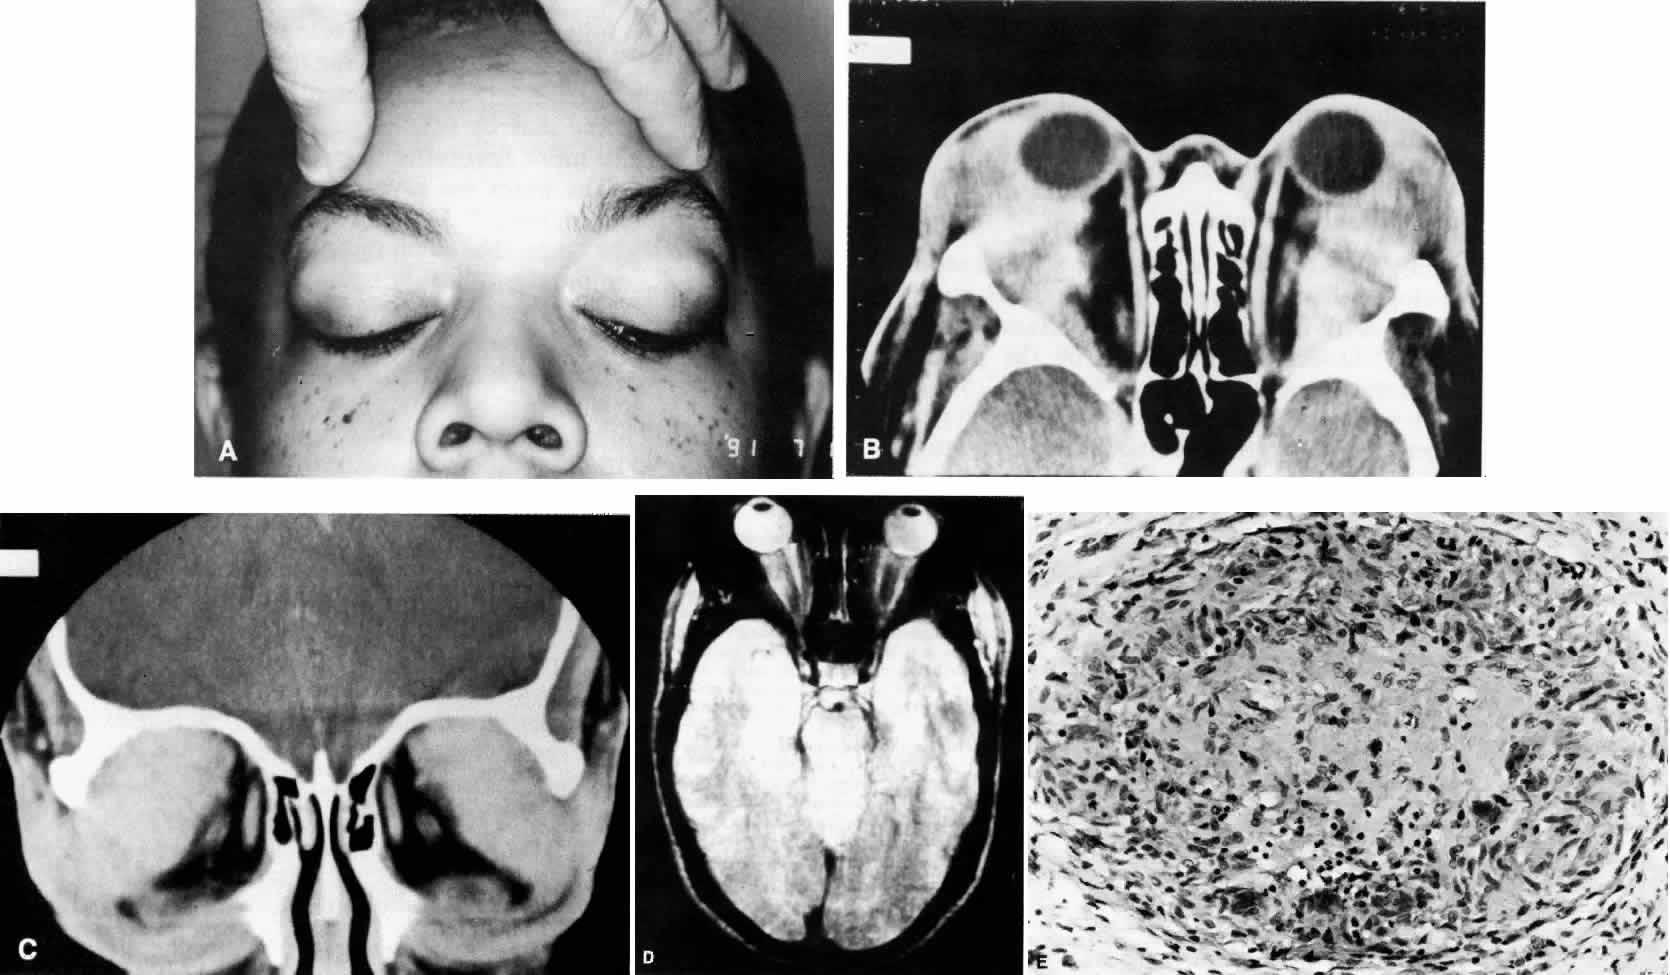

NODULAR FASCIITIS

Nodular or pseudosarcomatous fasciitis, while not usually considered part of the spectrum of idiopathic orbital inflammation, represents a localized inflammatory disease of idiopathic origin. It appears to be a reactive process involving a proliferation of immature connective tissue elements along with acute and chronic inflammatory foci (Fig. 7).102–106 This entity has been reported periorbitally in the eyelid as well as in the epibulbar tissue. It may also occur in the anterior or deep orbit. It appears as a rapidly growing mass arising over several weeks or months. It may or may not be associated with pain. At surgery, the lesion appears fairly well demarcated and slightly reddish.

Histopathology

Microscopically there is a proliferation of immature and active-appearing fibroblasts within the orbital fascial planes.102–106 These fibroblasts may be loosely connected with occasional myxoid foci interposed. Slits often appear between the fibroblasts, which appear to be quite plump and have basophilic cytoplasm. There may be rare mitoses among these cells. Only a minimal amount of collagen deposition is present. The appearance of a gradient from immature fibroblastic elements to more mature fibroblasts is characteristic of this lesion. Also associated with this process is acute and chronic inflammatory cells, capillary and endothelial cell proliferation, and occasional giant cells. Occasionally elements of this inflammatory process can be seen to invade surrounding muscle fibers and orbital fat. The proliferating capillaries are friable and bleed. When this occurs, hemosiderin-laden macrophages can be identified in the tissue. Electron microscopic evaluation of the cells present in this process shows that most are myofibroblasts. These are cells containing rough endoplasmic reticulum and no basement membrane like fibroblasts but also cytoplasmic actin filaments with fusiform densities like smooth muscle cells.3